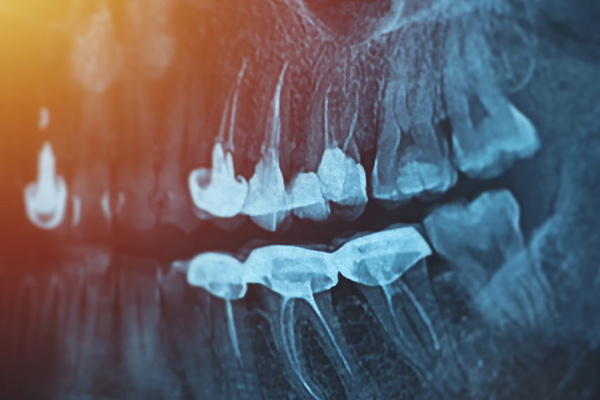

虫歯を全て取りきった状態で、どのくらい歯が残っているかが歯を残せるか残せないかの基準になります。歯を残すには、歯茎の上に最低2mm以上歯が残っていることが望ましいです。

歯茎の上に歯が残っていないと差し歯や被せものが外れやすかったり、歯が割れやすくなるため、将来的に抜歯になる可能性が高くなります。